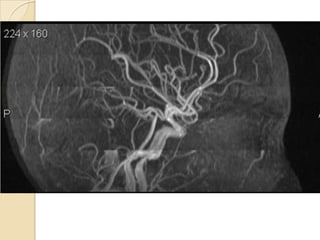

Arteries of the brain (lateral view) - MRA

1. Anterior cerebral artery

2. Anterior communicating artery

3. Basilar artery

4. branches (in insula) of middle cerebral artery

5. Cavernous portion of internal carotid artery

6. Cervical portion of internal carotid artery

7. Genu of middle cerebral artery

8. Intracranial (supraclinoid) internal carotid artery

9. Middle cerebral artery

10. Ophthalmic artery

11. Petrous portion of internal carotid artery

12. Posterior cerebral artery

13. Posterior cerebral artery in ambient cistern

14. posterior cerebral artery in interpeduncular

cistern

15. Posterior communicating artery

16. Posterior inf cerebellar artery.

17. Quadrigeminal portion of posterior cerebral

artery

18. Superior cerebellar artery

19. Vertebral artery